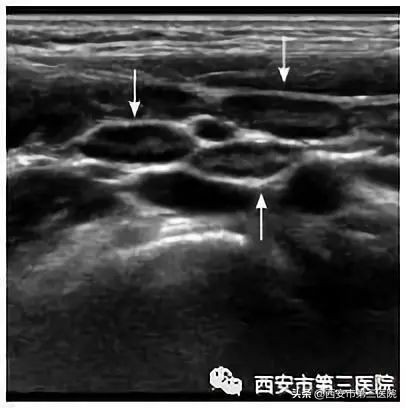

超声检查针对各种原因导致的小儿腹痛有很大的鉴别作用,小孩子腹痛最常做的辅助检查是超声检查,而且因为其简单、快捷而成为越来越常规的检查。肠系膜淋巴结炎超声检查会很直观的在小儿腹腔内探及明显异常的淋巴结声像图,这针对临床诊断有很大的帮助。